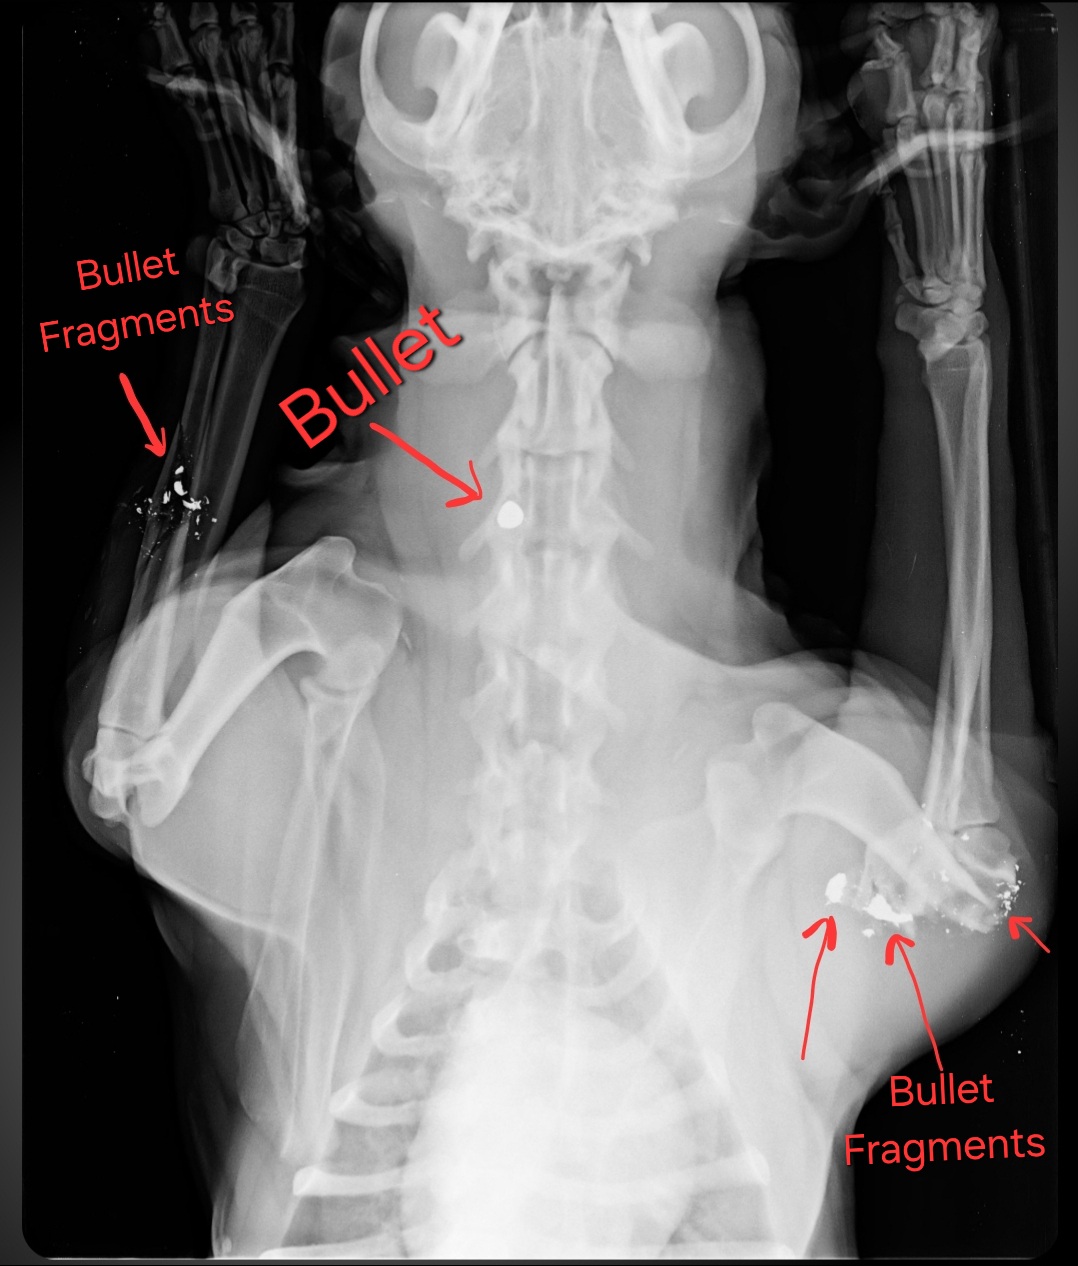

Gizmo's right front leg is shattered at the elbow. It can't be surgically repaired, so it will definitely require amputation. His left front leg is fractured but is still set properly, so the vet said they will splint it for 6-8 weeks to let it heal before they do the amputation. She wants to give him time to regain strength in

his left leg first. He also has bullet fragments in both legs and a bullet lodged near his spine on his neck, which will have to be removed. On top of all of that, she suspects Gizmo has heartworms, though that hasn't

been confirmed with the appropriate test.

The hard part first...Gizmo was actually shot twice. Once by a pistol and once by buck shot. Someone literally tried to kill him, but he refused to die! Furthermore, in spite of this, he remains his happy and loving self. He just wants to stay right by my side. Dont worry Giz I'm locked in for this journey. Love will conquer evil every time.